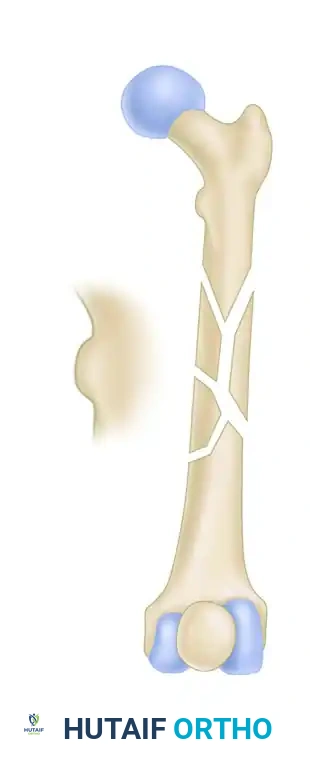

FIGURE 55-48: Proximal femoral locking plate fixation of a subtrochanteric femoral fracture with proximal extension. (A) Preoperative radiograph. (B) Preoperative axial CT scan shows extension proximally into the piriformis fossa. (C and D) Postoperative AP and lateral radiographs after fixation with a locking plate.

FIGURE 55-49: Fixation of a subtrochanteric nonunion with a blade plate. (A) Preoperative radiograph demonstrating hypertrophic nonunion. (B and C) Postoperative radiographs after rigid fixation and compression with a blade plate.